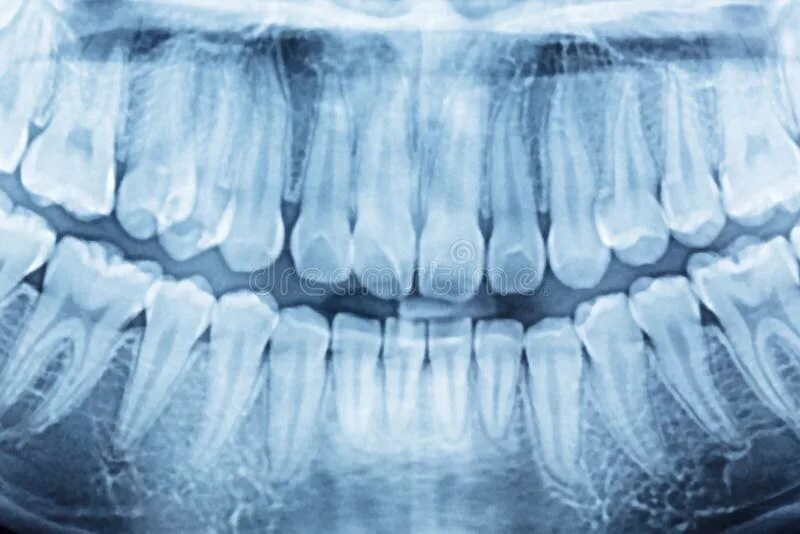

Снимок ротовой полости